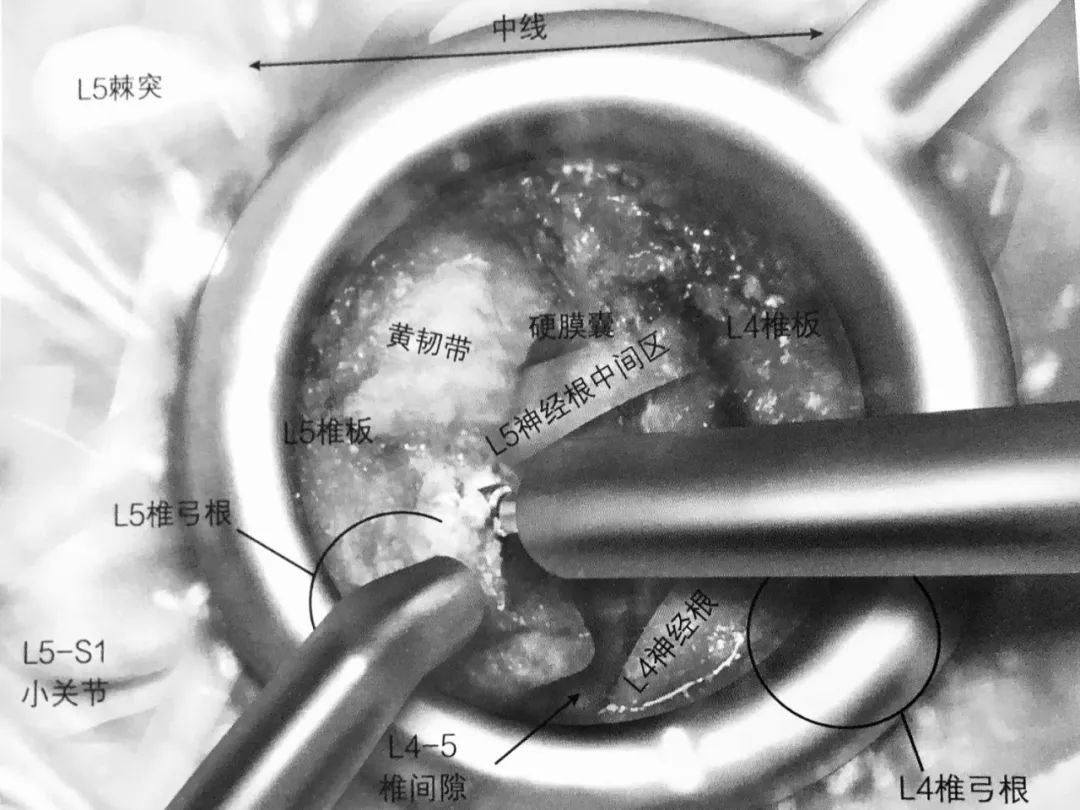

7. 应用双极电凝凝结椎间隙静脉丛止血。

8. 一旦完成静脉丛电凝止血,下位的椎弓根(L5)及 L4-5 椎间隙就能看得很清楚。L5 神经根中间部就在椎弓根内缘。L4 神经根出口就在椎间隙上缘,但并不一定需要显露。

9. 经椎间孔椎间融合术(TLIF)操作空间在椎间孔上位神经根出口的内侧。准备椎间植骨需要在侧位透视下进行。